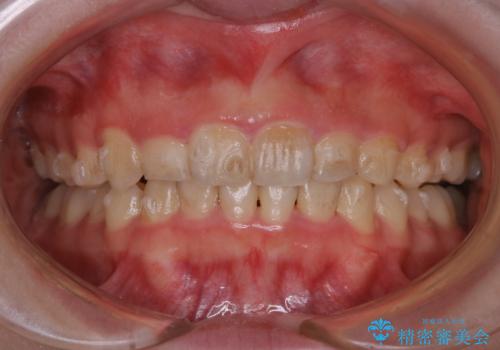

インビザライン中にステインの除去

- インビザラインでのマウスピース矯正中の方で、歯の表面のステインをきれいに取りたいとのことでした。PMTC60分コースを行いました。

PMTC(保険外治療)は、毎日の歯磨きで落としきれない汚れや、コーヒ、紅茶・タバコのヤニなどの着色も除去します。目には見えない歯と歯の間・歯肉の境目・インビザライン中はアタッチメント周囲などに残っているプラーク(歯垢)もしっかり取り除きます。PMTCでは専門的な機械や材料を使用して、徹底的に汚れを除去するため、虫歯・歯周病・口臭予防などにつながります。

またPMTCを行うことで、ご自身本来の歯の色になり自然な明るさになります。